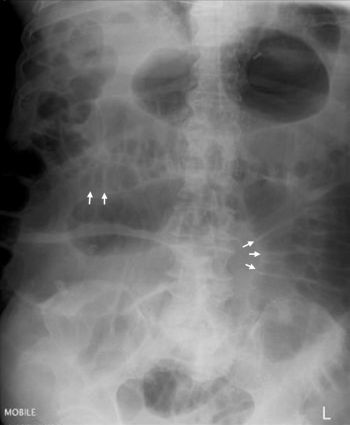

what is this condition

SIGMOID VOLVULUS: ‘coffee bean’ sign, starting in L iliac fossa pointing to RUQ